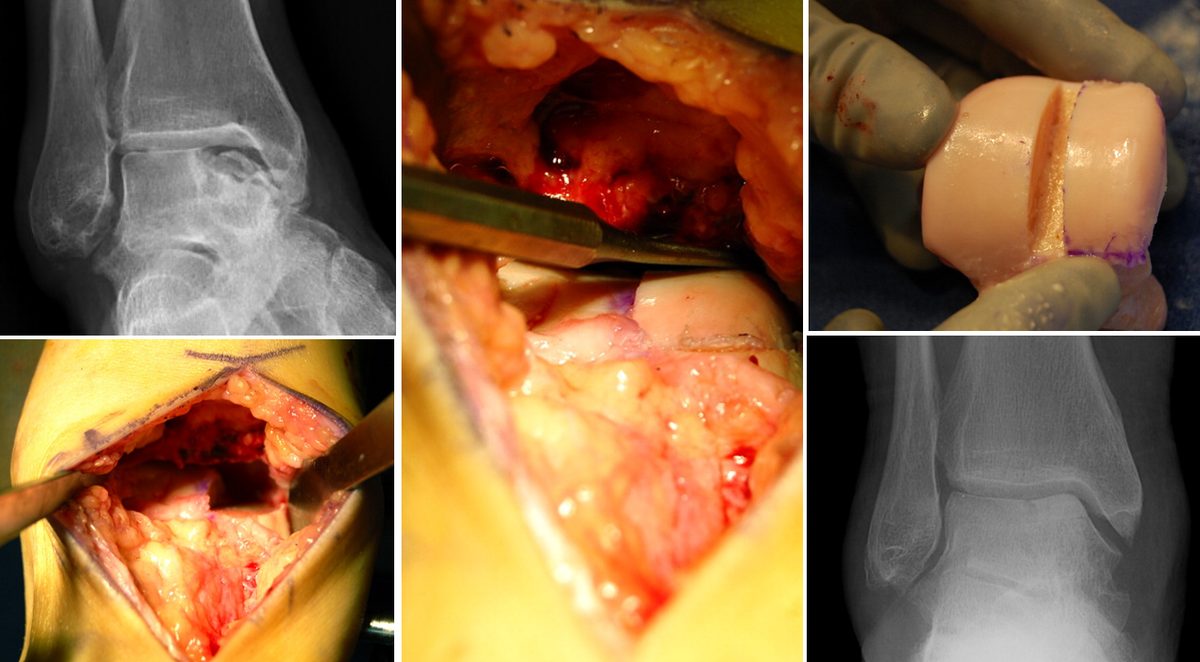

Аутологичная остеохондральная трансплантация (OCT / OATS)

Пересадка остеохондральных цилиндров (костно-хрящевых блоков) из ненагружаемой зоны коленного сустава в дефект на таранной кости.

Принцип: единственный метод, обеспечивающий пересадку живого гиалинового хряща с субхондральной костью в одну операцию.

Показания:

- Неудача BMS/M-BMS

- Крупные дефекты с значимым костным компонентом

- Кистозные повреждения с разрушением субхондральной пластинки

Техника:

- Забор остеохондрального цилиндра (6-10 мм в диаметре) из ненагружаемой зоны медиального мыщелка бедренной кости или межмыщелковой ямки

- Подготовка реципиентного ложа на таранной кости — формирование гнезда под цилиндр. Требуется строго перпендикулярный доступ к дефекту, поэтому часто необходима остеотомия внутренней лодыжки

- Имплантация цилиндра — press-fit фиксация, без дополнительных имплантов. Цилиндр должен быть заподлицо с окружающим хрящом (± 1 мм)

- Фиксация остеотомии (2 канюлированных винта)

- При множественных/крупных дефектах — мозаичная пластика (mosaicplasty): несколько цилиндров меньшего диаметра

Альтернатива: полностью артроскопическая техника — описана для центральных и передне-медиальных дефектов. Ретроградная имплантация через передние порталы. Позволяет избежать остеотомии, но технически сложнее и ограничена доступностью задне-медиальных зон.

Результаты:

- Хорошие/отличные у 87% пациентов

- Выживаемость 77,9–94% при наблюдении >10 лет [Grade B, Level III]

- Осложнения: 8% (наибольшая частота среди методов) [Grade B, Level III — мета-анализ 6962 ОХП]

- Донорская морбидность: 6,7–16,9% (в среднем ~9%) (боль в коленном суставе, ограничение функции). Основная проблема метода.

- Остеотомия внутренней лодыжки оказывает минимальное влияние на клинический результат [Grade C, Level IV — DGOU 2024]

Рис. 12. Мозаичная остеохондропластика (OATS) — пересадка остеохондральных цилиндров

Остеотомия внутренней лодыжки — необходима для доступа к задне-медиальным повреждениям (зоны 7-8) и при крупных дефектах (> 1.87 см²), требующих перпендикулярного доступа для остеохондральной трансплантации.

Типы остеотомии:

- Двуплоскостная шевронная (biplane chevron) — наиболее распространённая, обеспечивает широкий доступ и стабильную фиксацию

- Step-cut — ступенчатая остеотомия; хорошая ротационная стабильность

- Остеотомия передней 1/3-2/3 лодыжки — щадящий вариант, уменьшает риск повреждения сухожилия задней большеберцовой мышцы

Фиксация — 2 канюлированных винта (3.5-4.0 мм) или 1 позиционный винт + 1 К-спица. По данным DGOU 2024, остеотомия внутренней лодыжки оказывает минимальное влияние на долгосрочный клинический результат. [Grade C, Level IV]